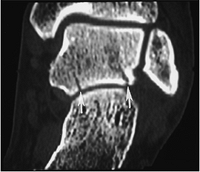

Fractures/Dislocations: Ankle Fractures—Pediatric: Triplane Fracture

-

Triplane fractures are the result of external rotation forces and account for 6% of physeal fractures.

The fracture consists of three fragments instead of two seen with most growth plate fractures.

Fracture fragments include (1) anterior

lateral tibial epiphysis (Salter-Harris III); (2) remainder of the

tibial epiphysis with metaphyseal attachment (looks like Salter-Harris

II); and (3) tibial metaphysis. -

Complication rates are similar to those for a Salter-Harris Type IV fracture.

CT may be required to properly characterize the injury.

![]() |

|

FIGURE 6-5 AP (A) and lateral (B) radiographs demonstrate a triplane fracture (arrows). Coronal (C) and sagittal (D) reformatted CT images define the fractures (arrow) and degree of displacement.